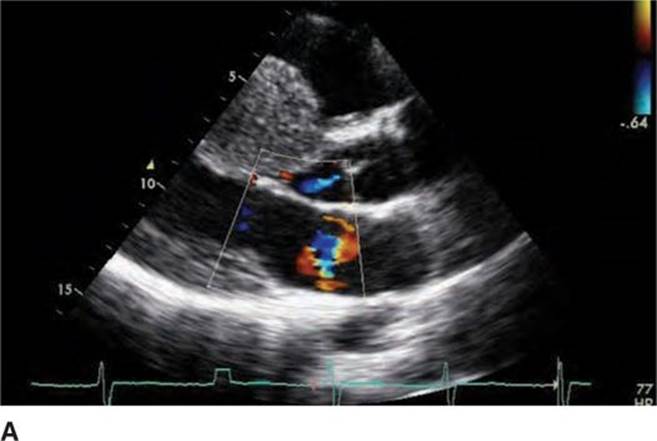

Physical examination revealed a systolic murmur that worsens with rapidly standing, squatting, and standing again. A 12-lead ECG reveals prominent QRS voltage in the precordial leads with deep T-wave inversions (Figure 53-1). An echocardiogram was obtained demonstrating a nearly 5 cm ventricular septum and mitral regurgitation secondary to systolic anterior motion of the mitral valve (SAM) (Figures 53-2 to 53-5). A resting left ventricular outflow tract (LVOT) gradient of 45 mm Hg was recorded with a provocable gradient of >80 mm Hg (Figure 53-6).

FIGURE 53-4A Parasternal long-axis view with color Doppler in diastole demonstrating normal opening of mitral valve.

FIGURE 53-4B Parasternal long-axis view during systole with color Doppler demonstrating increased turbulent flow through the aortic valve with SAM and resulting mitral regurgitation.

Screening with transthoracic echocardiogram should be performed at the time of the initial evaluation and yearly thereafter in known HCM patients and is recommended at the time of initial screening of first-degree relatives to assess left ventricular systolic and diastolic function, wall thickness, and outflow tract gradients.1-3,5 The obstruction that occurs in HCM has been shown to be due to mitral valve systolic anterior motion (SAM) with mitral-septal contact (best illustrated in Figures 53-5 and 53-7B), muscular obstruction in the midcavitary region, or anomalous papillary muscle insertion into the anterior mitral leaflet.1,2,6 The peak LVOT or midcavitary gradient should be measured at rest, and if <50 mm Hg, the test should be repeated with provocative measures such as exercise, Valsalva maneuver, or potentially amyl nitrate, with the latter rarely required in the current era. Provocation with dobutamine infusion during echo is no longer recommended. Upon testing, one-third of patients will have a resting LVOT gradient >30 mm Hg (obstructive HCM), one-third will have resting gradients <30 mm Hg (nonobstructive HCM), and a final one-third will have normal resting gradients but provoked gradients >30 mm Hg (labile obstruction).1,2,6